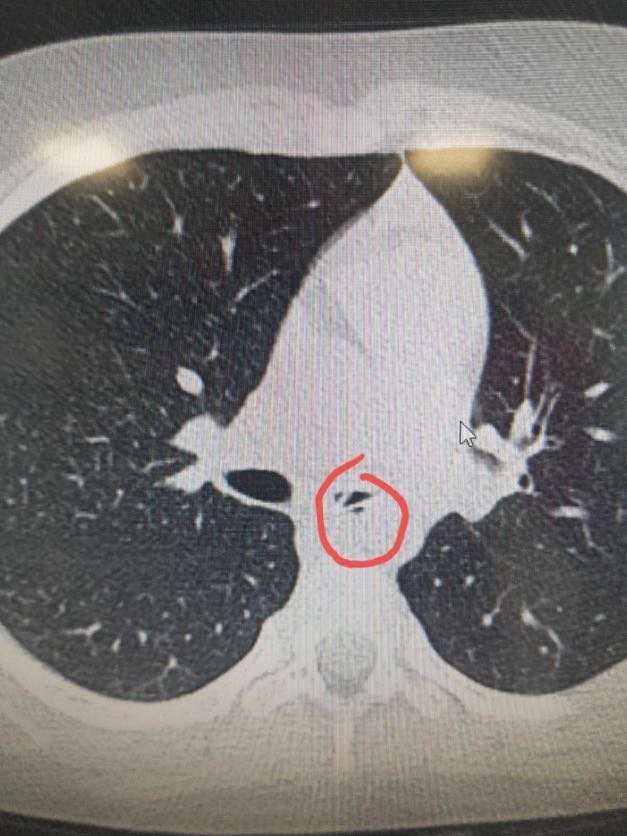

При обстеженні в НДСЛ «Охматдит» лікарі виявили стороннє тіло в дихальних шляхах Яни. Як виявилось потім, це була пластикова ложечка 4 сантиметри завдовжки.🥄

«Нетиповим було розміщення ложечки в лівому бронху. Адже майже завжди сторонні предмети потрапляють у правий бік. Також здивувало те, що дівчинці 6 років, - зазвичай подібні випадки трапляються з дітками віком до 3 років», – розповідає Сергій Руденко, завідувач педіатричного відділення Охматдиту.